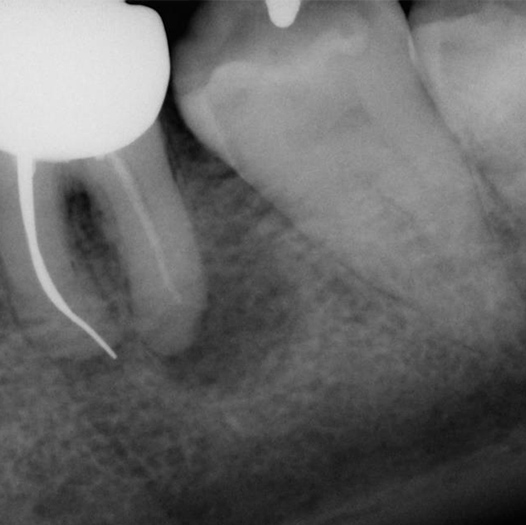

Before

Before Root Canal treatment